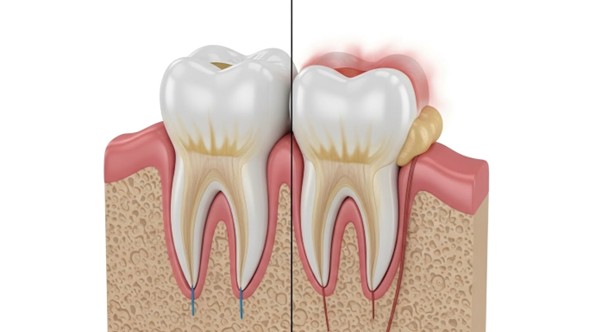

La gingivitis es la etapa inicial y más leve de la enfermedad de las encías. Se produce principalmente por la acumulación de placa bacteriana y sarro en la línea de las encías debido a una higiene oral deficiente. Lo más importante que debes saber sobre la gingivitis es que es reversible.

Cuando la placa no se elimina con el cepillado diario y el uso de hilo dental, se endurece y se convierte en sarro, el cual solo puede ser retirado por un dentista profesional. Las bacterias presentes en este sarro irritan las encías, provocando inflamación.

Si la gingivitis no se trata a tiempo, puede progresar hacia una periodontitis. Esta es una etapa mucho más grave y, a diferencia de la anterior, puede causar daños irreversibles.

En la periodontitis, la inflamación se extiende por debajo de la línea de las encías. Las toxinas de las bacterias y la respuesta natural del cuerpo a la infección comienzan a destruir el hueso y el tejido conectivo que mantienen los dientes en su lugar. Las encías se separan de los dientes, formando espacios llamados “bolsas periodontales” que se infectan aún más.

Hemos notado que muchos casos de pérdida dental en adultos no se deben a caries, sino a una periodontitis no diagnosticada a tiempo. A medida que la enfermedad avanza, los dientes pueden aflojarse y, finalmente, caerse o requerir extracción.